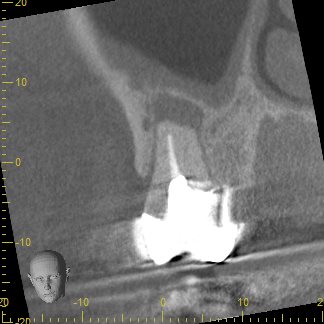

歯根周囲の骨の吸収が大きく、保存が可能かどうか判断が難しいと思われたCT画像

従来のレントゲン画像は全てのものが影絵として一枚の平面に写し出されるため、根の先の病巣の大きさを詳しく調べることが困難です。そこで、CT撮影を行うことで、3次元的に様々な角度で確認し、根の先の病巣がどれほどの大きさを調べその歯が保存可能なのかどうかを診ていきます。

この写真は術前のCT画像です。

歯根の周囲に見られる黒くなっている部分は、細菌の感染により骨が吸収しています。根尖病巣と呼ばれるこの部分が大きいほど治る確率が下がると言われ、根管内の細菌数も多いことがほとんどです。

ここまでの吸収があると、歯根が破折してる可能性を考える必要があります。